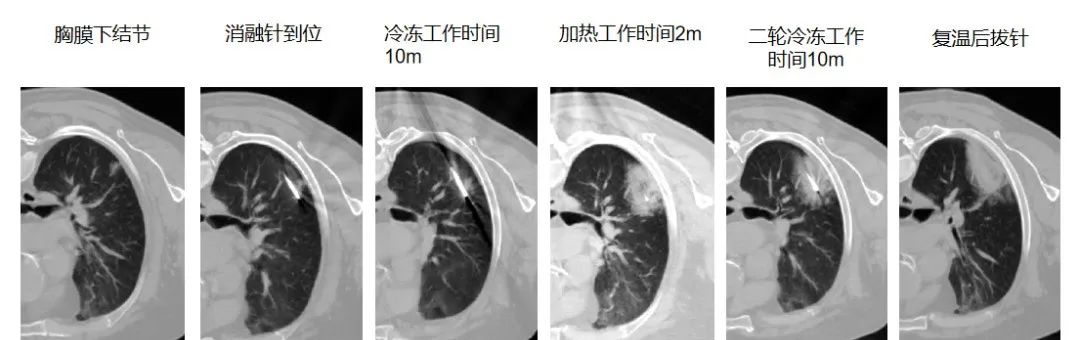

在国内率先开展冷热复合式消融技术

为肺部肿瘤的治疗

冷热复合式消融技术的独特之处首先体现在它以外科技术为核心,巧妙地融合了冷热复合式消融理念。在治疗过程中,科室依托先进的多学科协作诊疗(MDT)模式,组织多领域专家对患者的肿瘤特征、全身状况以及治疗耐受性进行全面而细致的综合评估。这种精准的评估体系能够根据患者的具体情况,在微创腔镜手术、介入消融等多种治疗策略中,为患者量身定制个体化的治疗方案。

针对肺部多发结节治疗难题,天津医科大学总医院肺部肿瘤外科创新推出 “胸腔镜微创 + 冷热复合式消融” 的 “杂交手术” 模式。该技术避免传统手术对肺功能的损伤,让无法单一术式根治的患者获得更彻底治疗,目前占科室消融治疗总量 10%,实现肺功能保护与肿瘤控制率双提升。在此基础上,科室将冷热复合式消融技术应用于局部晚期肺部肿瘤的姑息治疗,与靶向、免疫、放疗等手段结合,形成 “局部 - 全身” 全程化管理模式,有效缓解患者症状、控制病情、延长生存期。